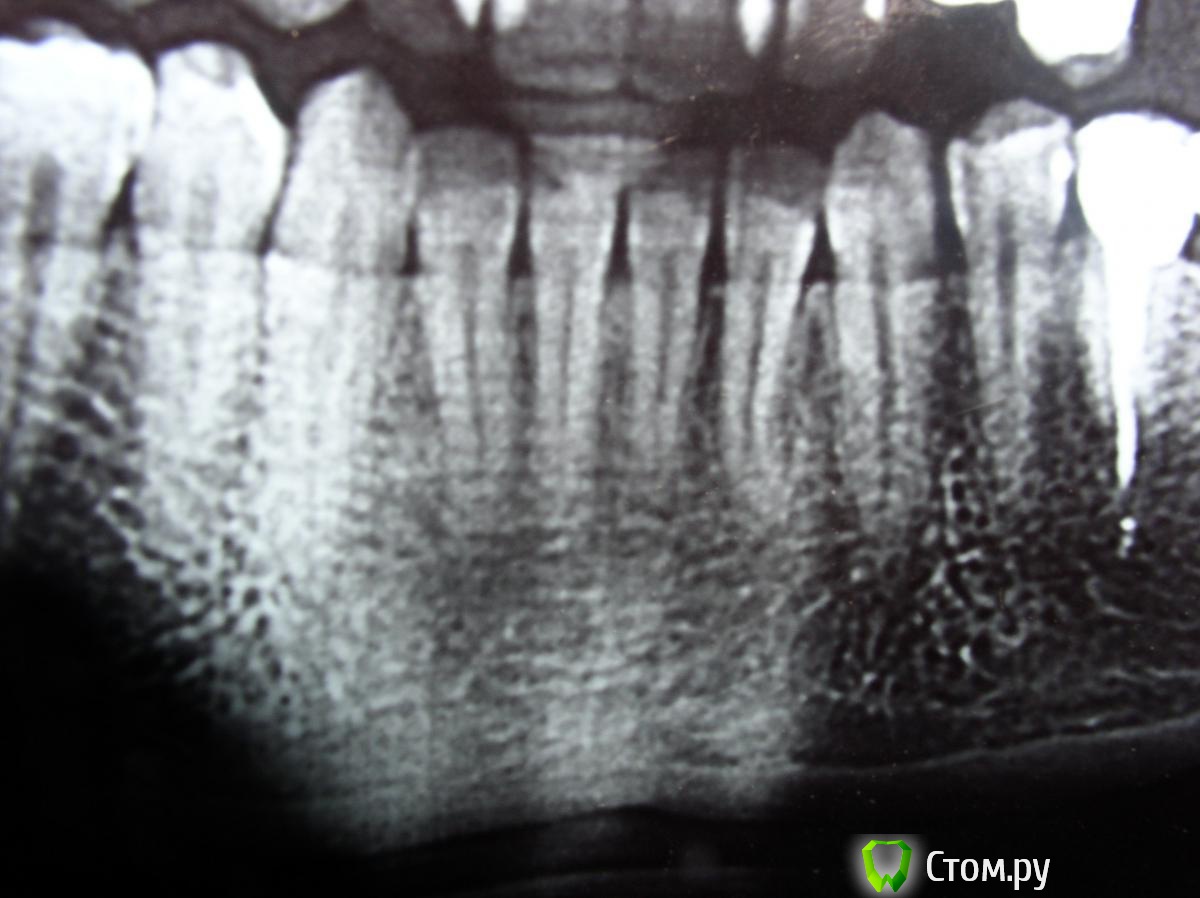

Stomart Опубликовано 19 ноября, 2014 Поделиться Опубликовано 19 ноября, 2014 Сделайте прицельный снимок, этот плохого качества. 1 Ссылка на комментарий

anaG2011 Опубликовано 24 ноября, 2014 Автор Поделиться Опубликовано 24 ноября, 2014 Добрый вечер, в шестерке стоит временная пломба. Каналы перелечены. Ортопед предлагает в 6-ку поставить титановый штифт, а у пятерки заменить пломбу (штифт оставить, каналы не трогать).Поставить опять спаренную м/к коронку. http://s017.radikal.ru/i406/1411/89/fb325c36299a.jpg- прицельный рентген. снимок 5 и 6 http://s017.radikal.ru/i433/1411/fb/2089cd590e34.jpg- прицельный снимок 5 и 6 на визиографе Уважаемые доктора, посмотрите, пожалуйста, снимки, какое Ваше мнение? Ссылка на комментарий